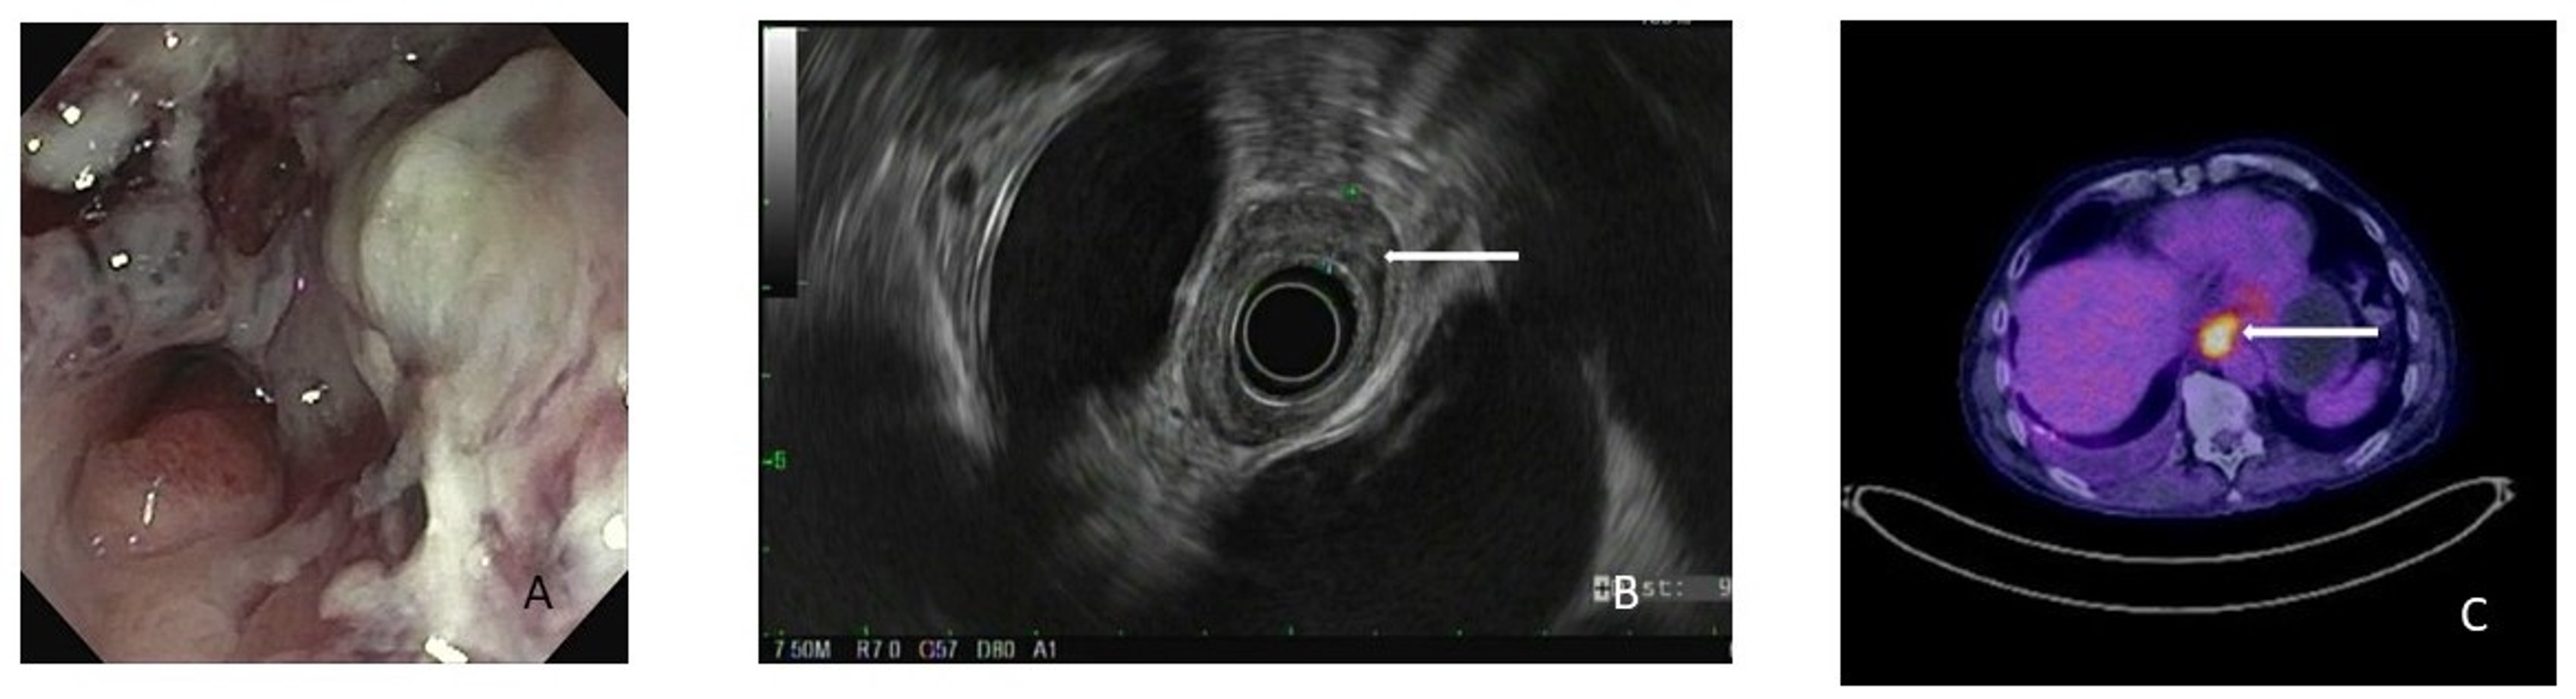

Upper gastrointestinal endoscopy showed a type 3 esophageal cancer... Download Scientific Diagram Endoscopy Of Esophageal Cancer Esophageal cancer may not cause symptoms early on. But in patients with early. Read about types of treatment for esophageal cancer that can be done by passing an endoscope (a long, flexible tube) down the throat and into. During an upper endoscopy, you are sedated (made sleepy) and. A distinct advantage of resection over ablation therapy is the. An endoscopy. Endoscopy Of Esophageal Cancer.

Endoscopic ultrasound view of a T1b esophageal cancer. The cancer... Download Scientific Diagram Endoscopy Of Esophageal Cancer Symptoms of esophageal cancer usually happen when the disease is. This is an important test for diagnosing esophageal cancer. An endoscopy offers an opportunity to collect tissue samples (biopsy) to test for diseases and conditions that may be. During an upper endoscopy, you are sedated (made sleepy) and. But in patients with early. Esophageal cancer may not cause symptoms early. Endoscopy Of Esophageal Cancer.